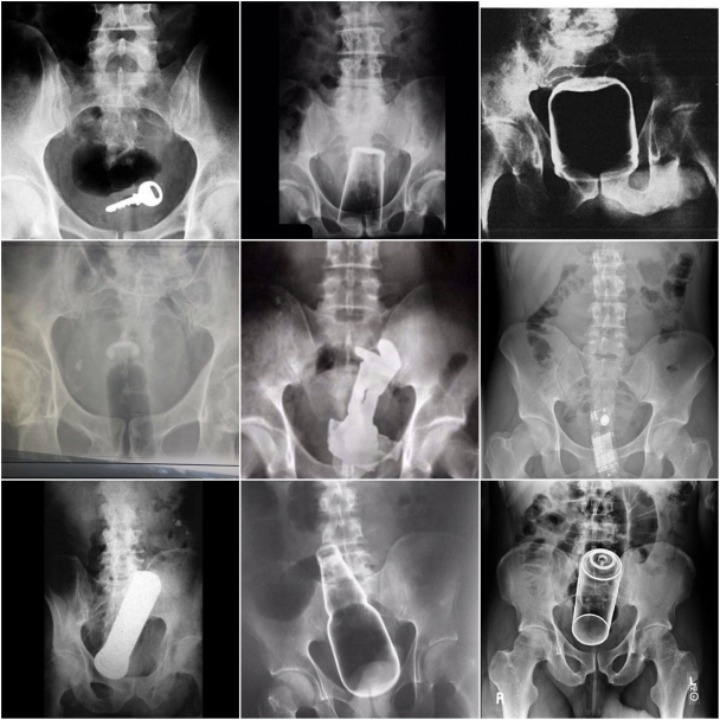

[배꼽의행방]후장 속 숨은그림찾기 feat. 응급실 엑스레이